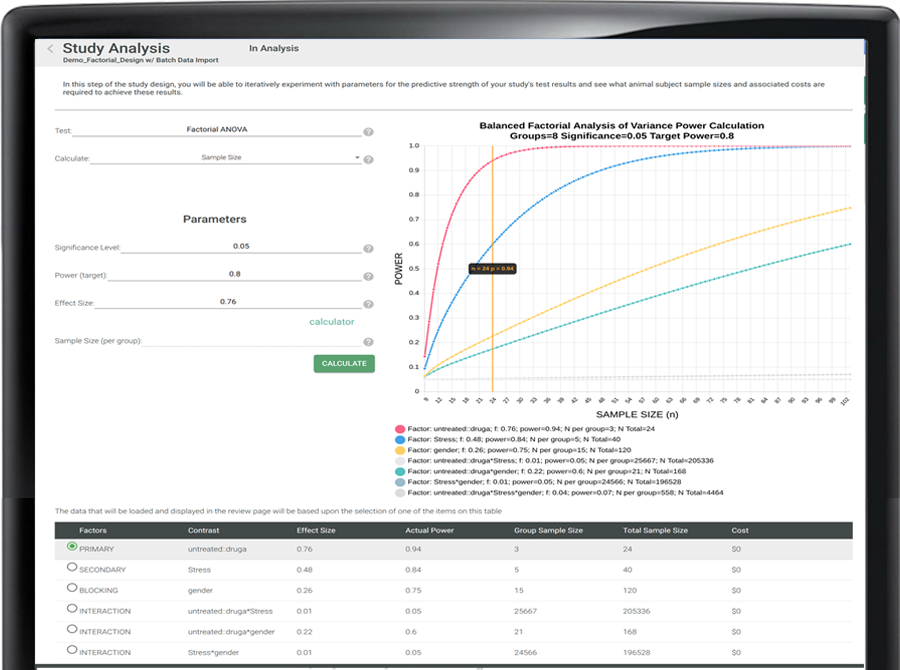

Define experimental design, assumptions, and statistical intent with confidence.

Many downstream study issues originate at the design stage—unsupported assumptions, unclear endpoints, or inappropriate statistical models. Seralogix addresses these risks before data collection begins by embedding AI-assisted guidance directly into experimental design workflows.

Selections such as shared subjects, repeated measures, or secondary factors are interpreted in context so design consequences are clear early.

Leverage public reference data or prior internal studies to refine effect size and variability assumptions without overwriting scientific judgment.

Choose validated study patterns—t-tests, repeated measures, ANOVA, factorial designs—and Seralogix guides structure, timelines, and required fields so the workflow matches the science.

Link response factors to prior results from public datasets or your organization’s history to refine variability and effect size assumptions—without overwriting scientific judgment.

Update assumptions as new data accumulates, compare scenarios, and preserve versioned decisions—so studies improve continuously while maintaining audit-ready traceability.

study driven objects and goals sets testing requirements (e.g., t-test, repeated measures, factorial)

Improved assumptions improves the power of a study (e.g., effect size, outcome response variability, other sources of variability)